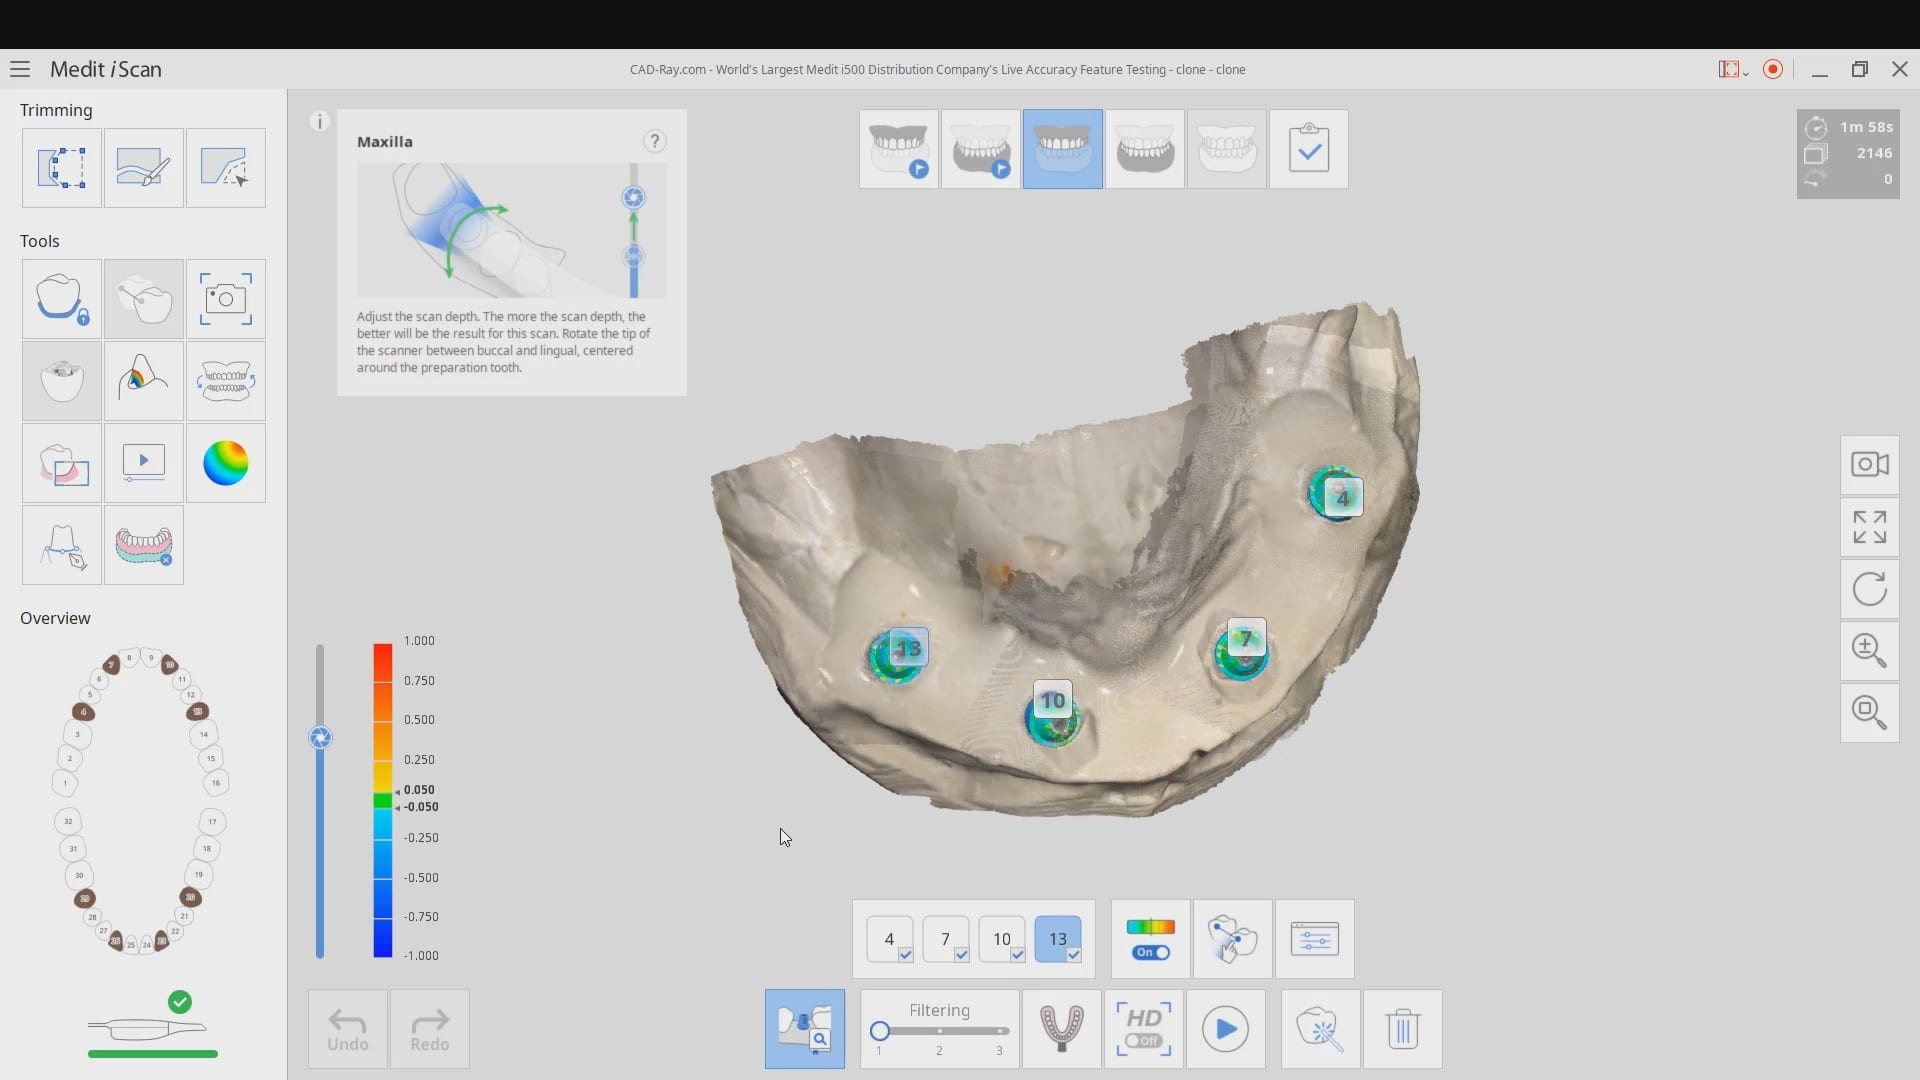

Live Intra-Oral Scan Verification Jigs for Full Arch Scans and Global Accuracy

October 25, 2019This is a detailed video demonstration that shows you how to capture full arch scans for multi unit implant cases in edentulous jaws and, more importantly, how to assess its […]